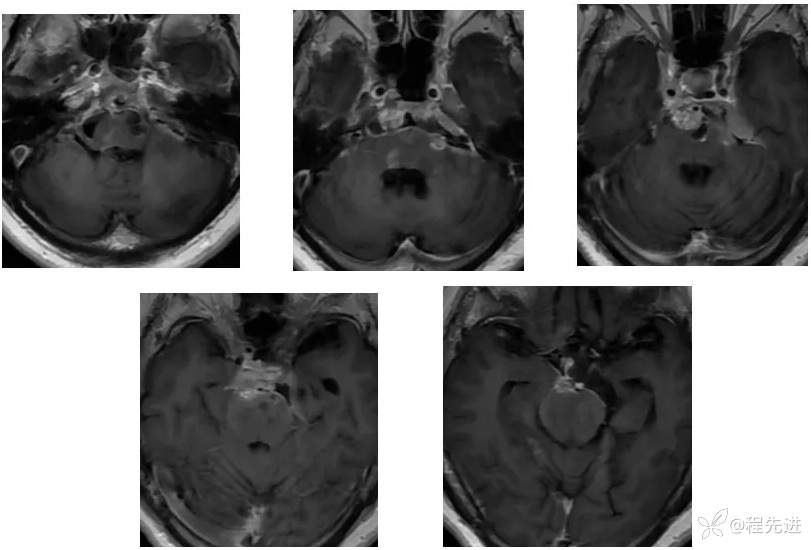

【神经】特别精彩病例|右眼斜视及视力下降7个月,右眼脸下垂3个月,右眼失明1个月

【患者信息】:女,62岁

【现病史及既往史】:右眼斜视及视力下降7个月,右眼脸下垂3个月,右眼失明1个月

【检查】:

查体:生命体征平稳,右眼脸下垂,右眼失明,左眼内收位,外展受限,光反应迟钝,左侧角膜反射减弱,左侧听力下降,左面部痛温觉减弱无吞咽困难,无饮食饮水呛咳,伸舌舌尖左偏。